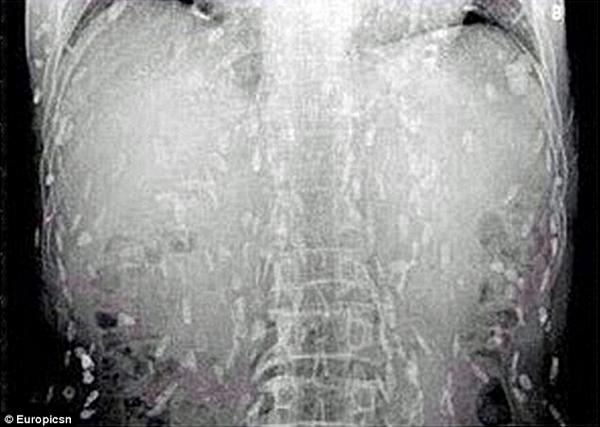

芽殖孤虫(Sparganum proliferum)とは人間に芽殖孤虫症を引き起こす寄生虫の幼虫。 世界で14症例が報告され、そのうち7例※が最初に発見された日本で起きている。 芽殖孤虫は体内では薄い嚢に包まれており、大きさは数ミリから ;芽殖孤虫 症状 芽殖孤虫(がしょくこちゅう、英:Sparganum proliferum)は、ヒトに寄生する人体寄生虫の1種。条虫綱擬葉目裂頭条虫科に属する扁形動物。成虫は同定されていないため、孤虫の名が付 · 芽殖孤虫 生活史 成虫が同定されていないため、は全く不明である。ヒトに寄生した場合、体内では成虫にはなれないため、幼虫移行症を起こす。また、この類ではよくある事であるが、幼虫のままで宿主体内で分裂して増殖す

鋒山 芽殖孤虫症 寄生虫が無性生殖を繰り返し身体中に寄生して行く 末期には身体の至る部分に寄生虫が詰まった水泡ができて死ぬ 何の幼虫なのかも全くわからないため治療法もない Http T Co Jeqstxymbs

頭痛と痙攣に悩む11歳少年の脳から寄生虫 中国の食肉に潜んでいた 芽殖孤虫 の恐怖

頭痛と痙攣に悩む11歳少年の脳から寄生虫 中国の食肉に潜んでいた 芽殖孤虫 の恐怖 14年12月11日 エキサイトニュース